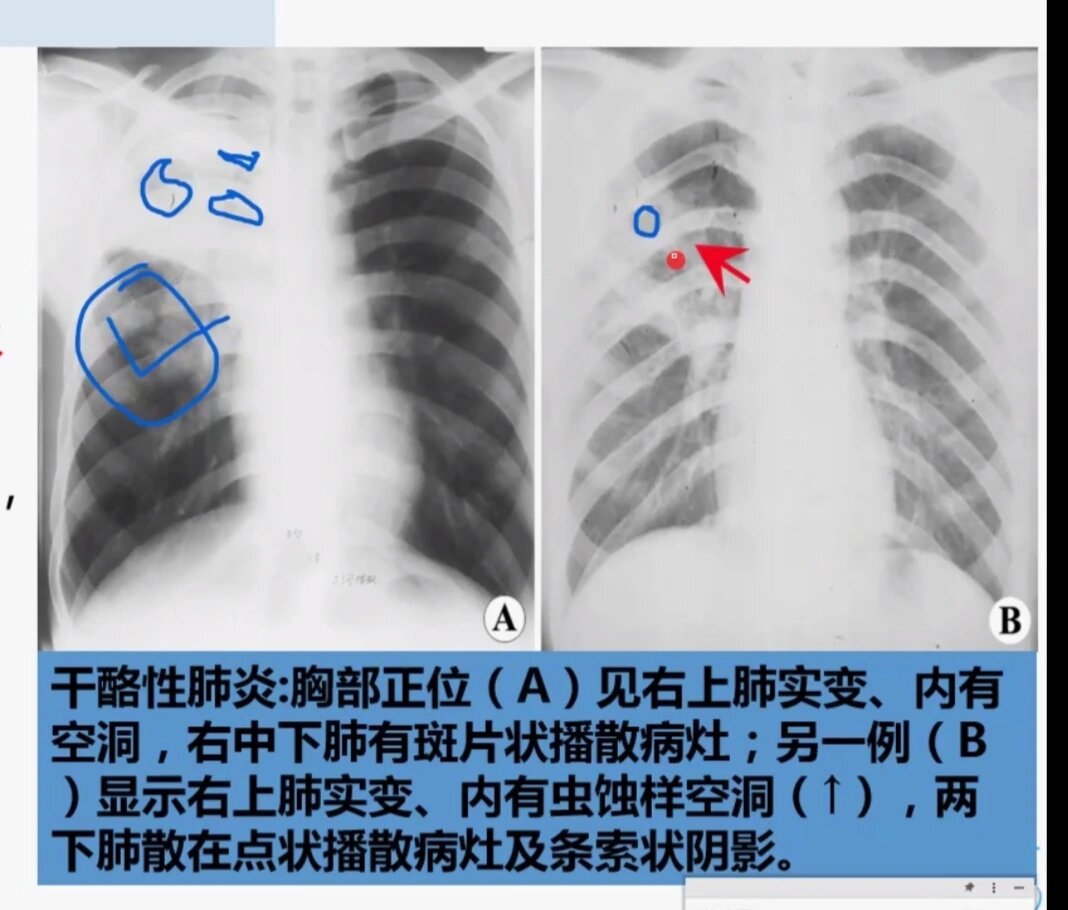

肺结核的影像学表现及鉴别诊断

肺结核的影像学表现及鉴别诊断

肺结核的影像学表现及鉴别诊断

肺结核的影像学表现及鉴别诊断

肺结核的影像学表现及鉴别诊断

肺结核的分型及影像学表现

肺结核的影像学表现及鉴别诊断